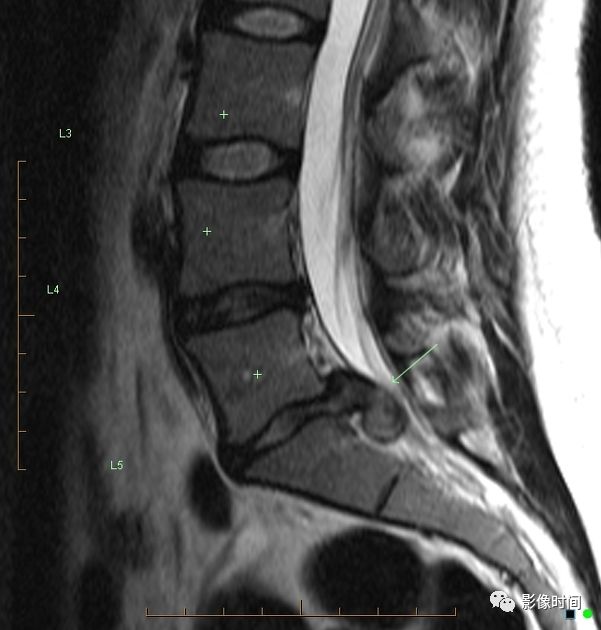

3双边征

双边征是脊柱前滑脱的 CT 表现之一,指的是在横轴位图像上,上位滑脱椎体下缘与下位椎体上缘显示于同一层面,位置一前一后,呈「双边」样。常见于腰椎椎弓峡部裂伴椎体滑脱。

典型病例

腰椎椎弓峡部裂并椎体滑脱。CT 示双侧椎弓峡部裂隙(红箭),并可见双边征(黄框)。

引用自:张杰,卜庆丰. 腰椎椎弓峡部裂的 CT 诊断. 中国医学影像学杂志,2005,13(6):467-468.